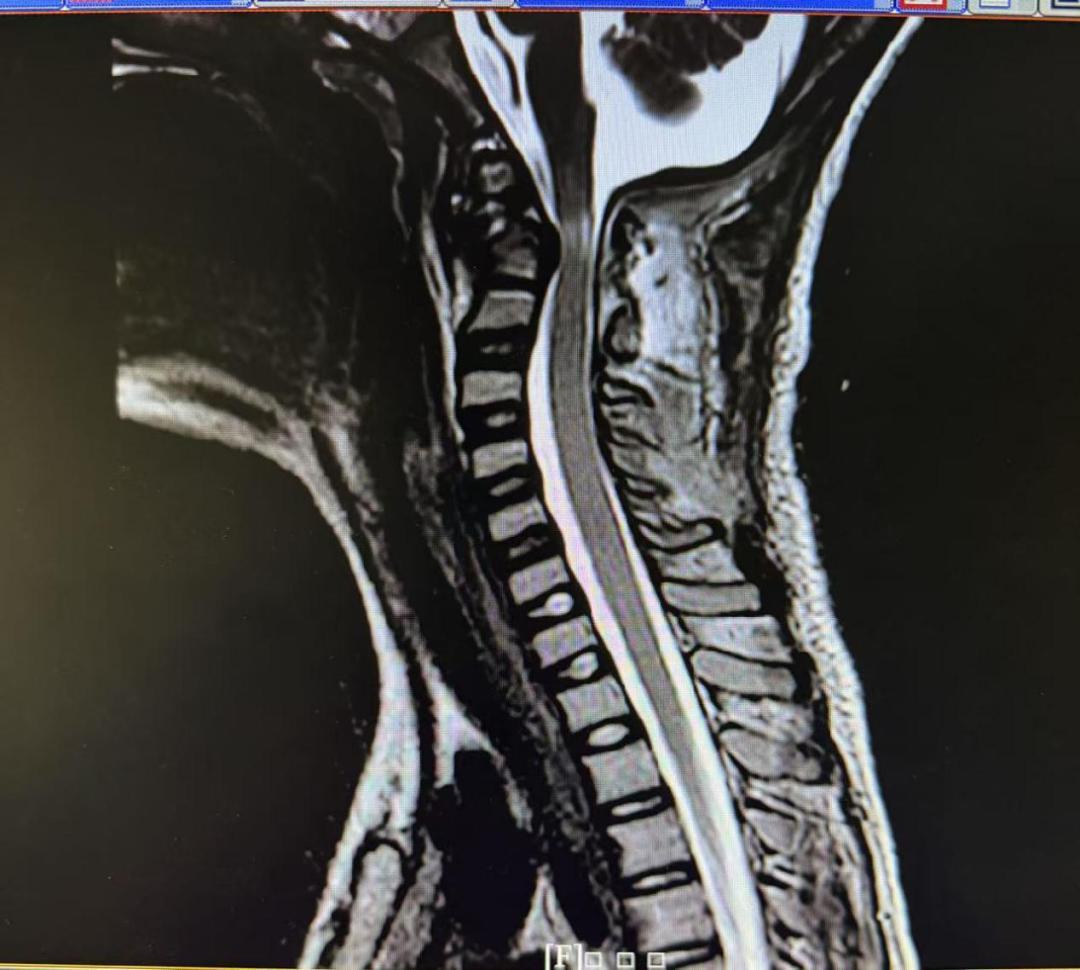

术前磁共振(脊髓明显受压),术后磁共振(脊髓受压解除)。

术后,医护团队为乐乐量身定制了康复方案:从最初的床上翻身训练,到辅助站立,再到步态练习和日常生活能力恢复,每一次进步都凝聚着医护人员的专业与爱心。术后一周,原先只能躺在平车上的孩子,终于带着自信的笑容,一步、两步,慢慢走向等候在病房门口的“家人”们。